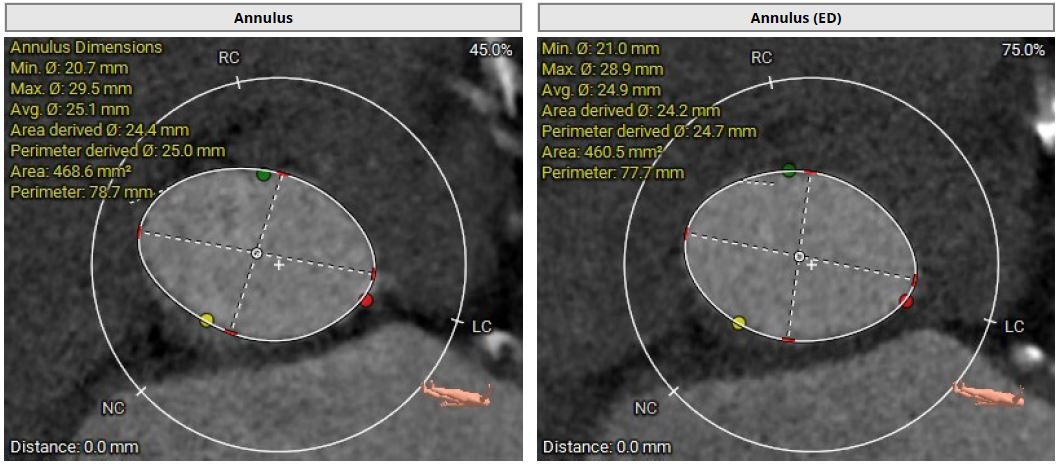

However, multislice CT scan revealed severe stenosis and calcific change in bilateral femoral arteries, making the transfemoral arterial approach unfeasible. Alternative access sites, including bilateral carotid and axillary arteries, were also not feasible. Although there was severe calcification in the abdominal aorta, the transcaval approach targeting a calcium-free segment of the aorta at the L3 level represented barely the last resort for carrying out TAVI procedures.